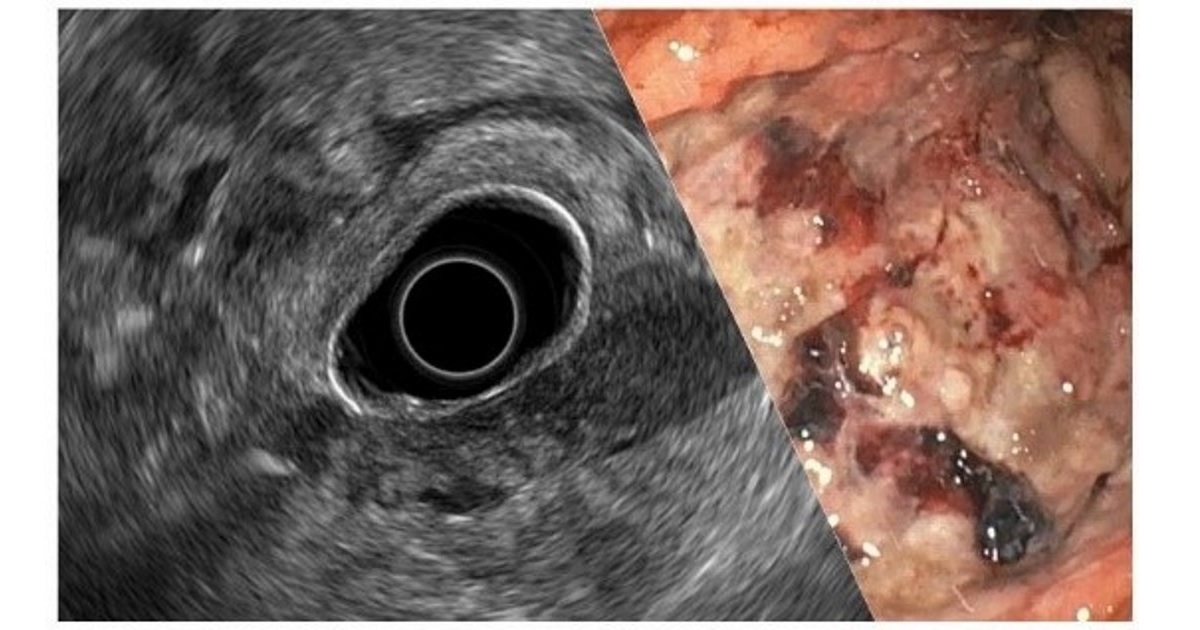

Cancers is launching a Special Issue focused on the role of endoscopy in gastrointestinal cancers. Endoscopy has shifted from having a central, but still limited, role in diagnosis to an increasing and exciting participation in cancer therapy. At present, endoscopy has not only a central role in therapeutic decision-making in gastrointestinal cancer, but a direct therapeutic involvement in the treatment and palliation of these diseases. For these reasons, a journal Special Issue especially dedicated to GI endoscopy in cancer is timely.

This Special Issue aims to publish papers covering novelties for the diagnosis of early cancers, such as colorectal cancers, upper GI tract tumors and biliary-pancreatic disease, as well as insights into staging and endoscopy-based therapeutic alternatives that have arisen in this rapidly evolving field.